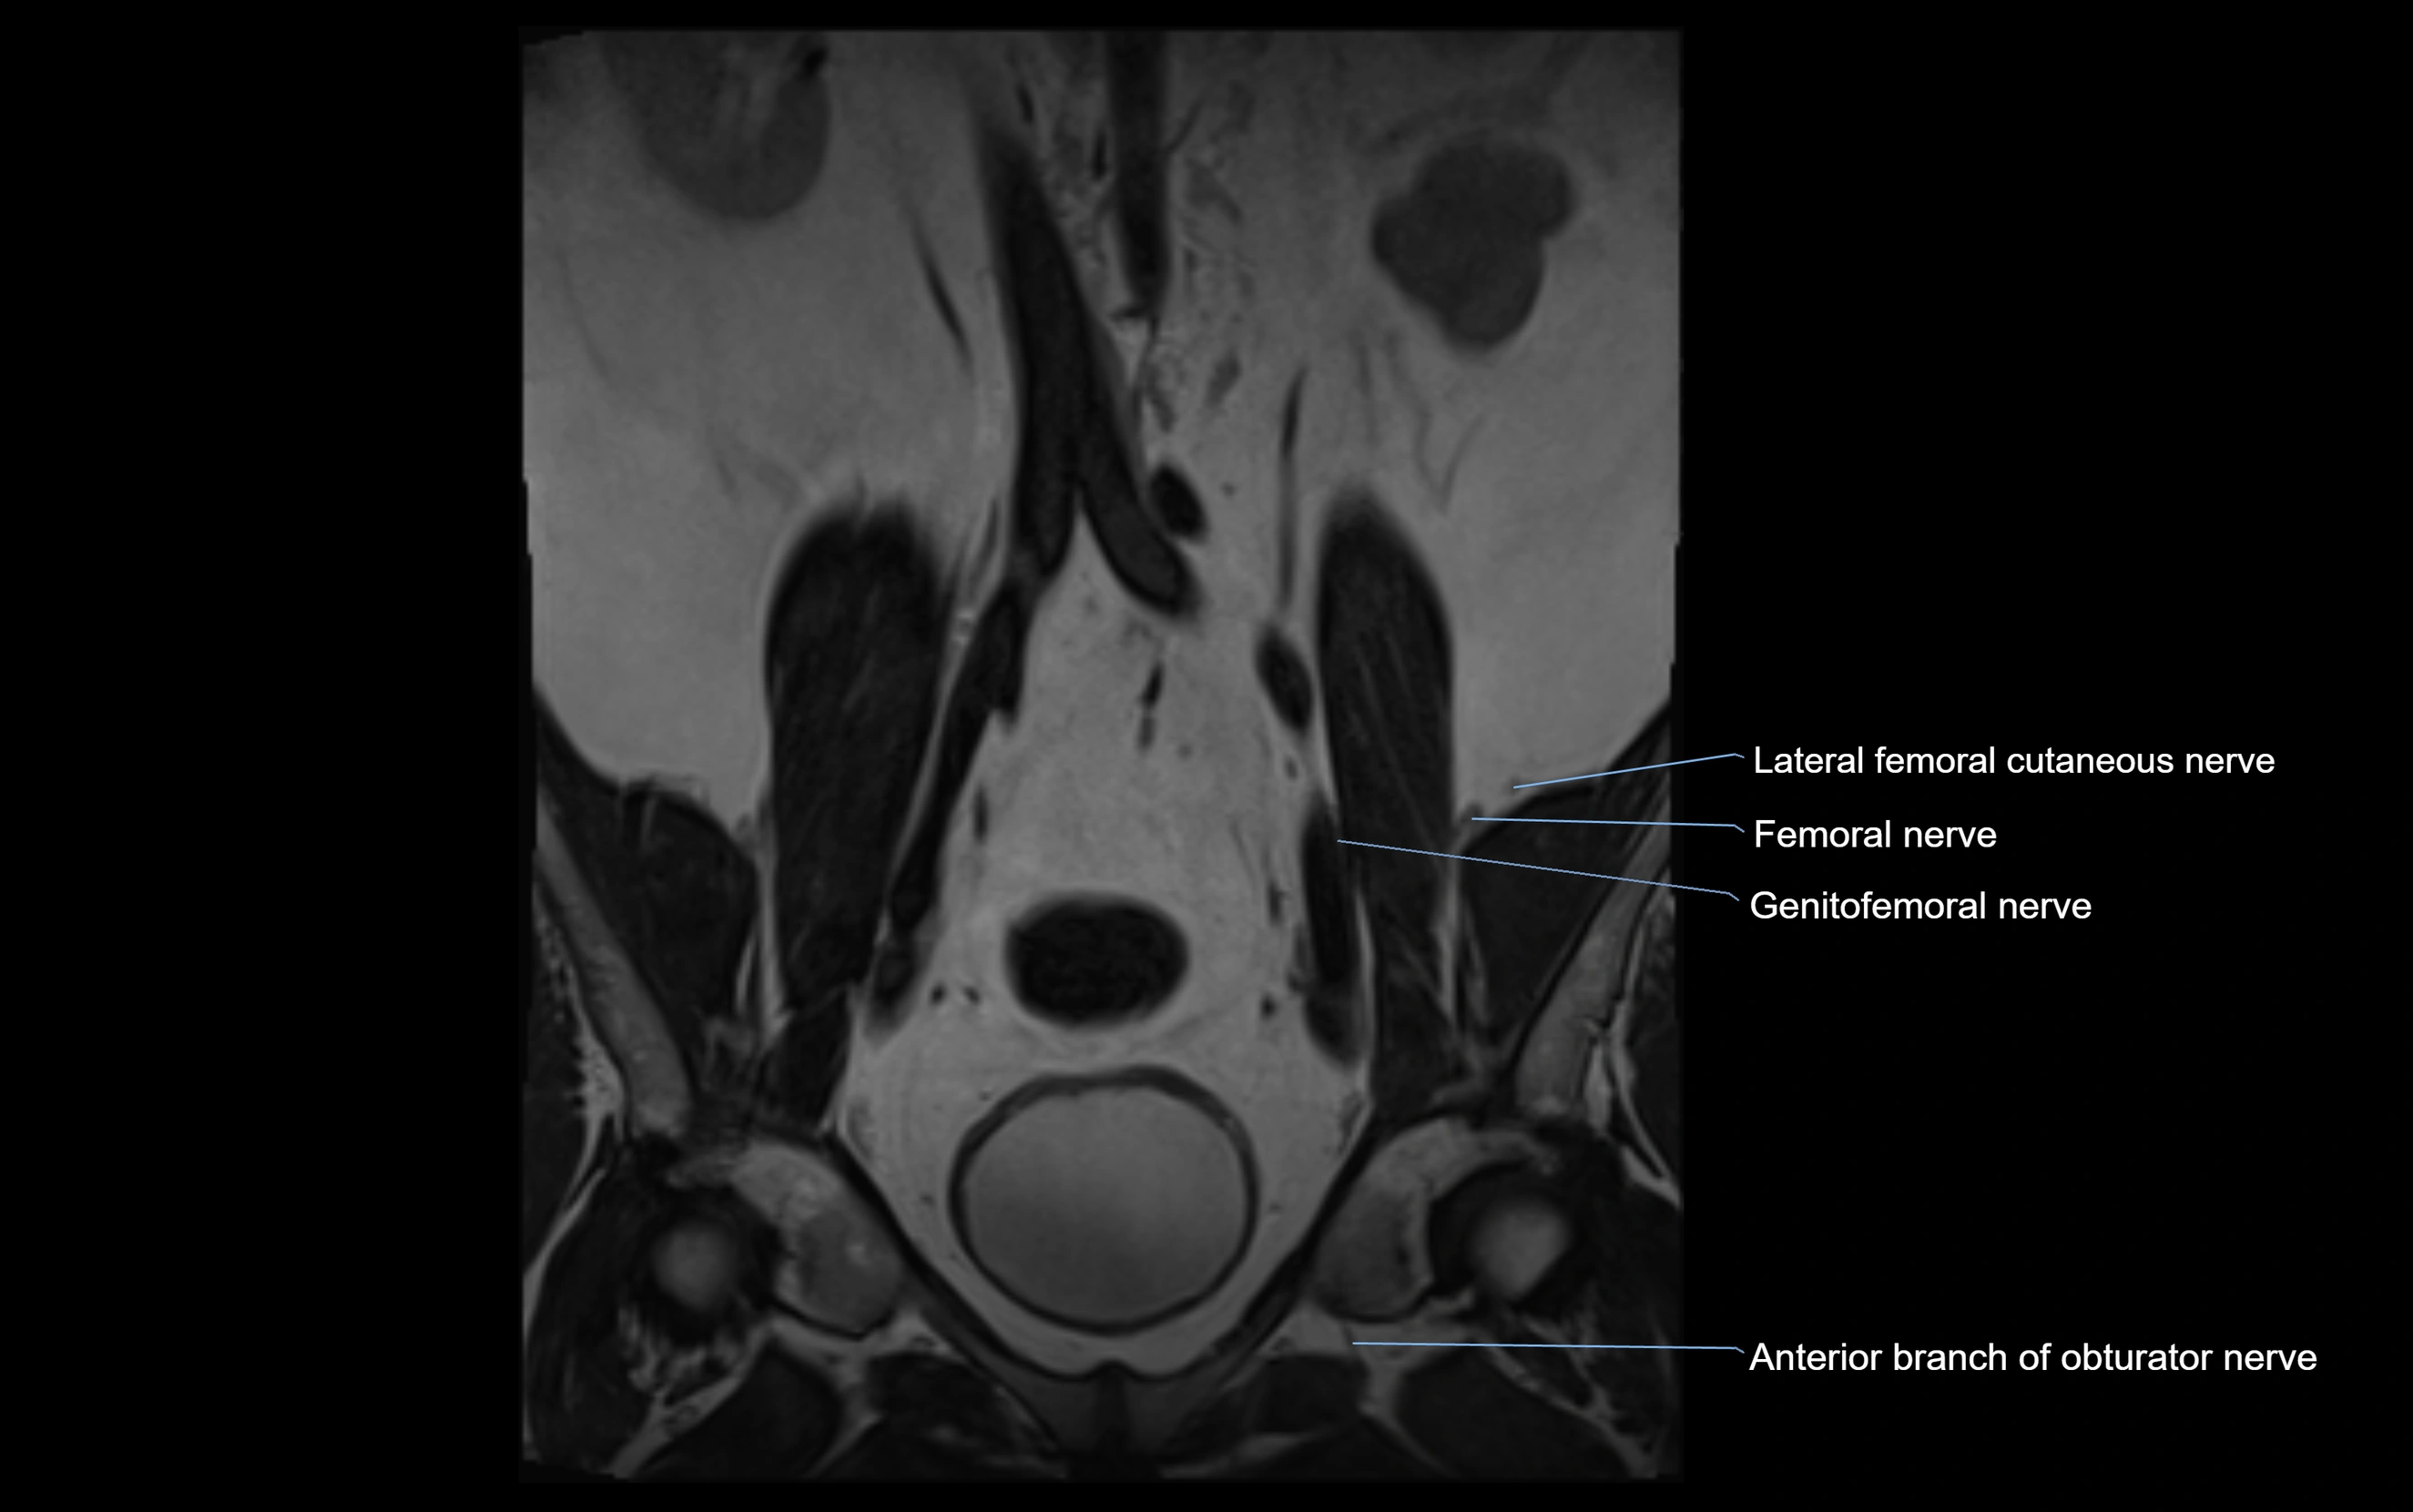

MRI Appearance

T1-weighted images:

• Nerve appears as a very thin low-to-intermediate signal intensity structure

• Surrounded by bright fat, aiding visualization

T2-weighted images:

• Nerve shows intermediate to mildly hyperintense signal compared to muscle

• Pathological involvement appears brighter

STIR (Short Tau Inversion Recovery):

• Normal nerve appears dark

• Inflamed or entrapped nerve appears bright hyperintense

T1 Fat-Sat Post-Contrast:

• Normal nerve enhances minimally

• Pathologic nerve (neuritis, entrapment, tumor infiltration) shows focal or diffuse enhancement

3D T2 SPACE / CISS:

• Nerve appears intermediate to mildly hyperintense compared to muscle

• Surrounded by bright fat or CSF, improving visualization

• Best sequence for mapping small pelvic nerves such as the anococcygeal

MRI image

image